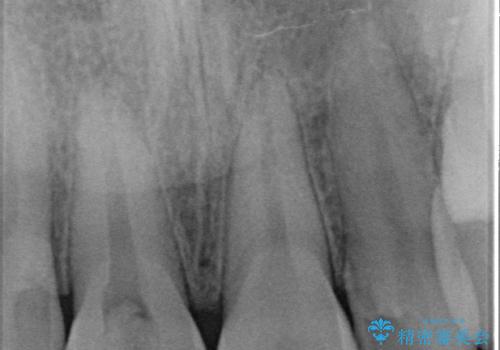

歯根破折により抜歯となってしまった奥歯のインプラントによる咬み合わせ回復

上顎洞までの距離が約7mmと、インプラント体の長さに比べ約3mmほど高さが足りなかったため、わずかに上顎洞粘膜を持ち上げてインプラントを埋入しました。

このような処置を併用した場合、2次手術までの期間を少し長めに待たなければなりませんが、最終的にしっかりと咬める状態となりました。

インプラントの種類:Zimmer spline

かぶせものの種類:Bellezza